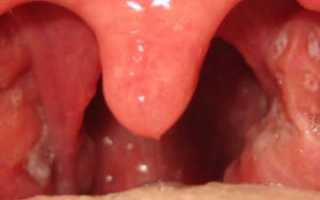

Ангина начинается с общего ухудшения самочувствия и лихорадки. Температура при ангине может достигать показателя 40°C. Наблюдается поражение гланд: покраснение и увеличение в размерах. На слизистой оболочки ротовой полости появляются участки язвенного поражения, которые постепенно начинают омертвевать. Их большое количество наблюдается на поверхности нёбных миндалин, а также в области зёва и дёсен. Ткани, поражённые некрозом, отторгаются организмов, после чего на их месте образуются глубокие шрамы. Усиливается процесс выделения слюны, появляется характерный запах гнили изо рта.

- Инструментальный осмотр глотки. Позволяют выявить поражение нёбных миндалин и отследить динамику развития воспалительного процесса в ротовой полости по числу и характеру язвенных и некротических поражений.